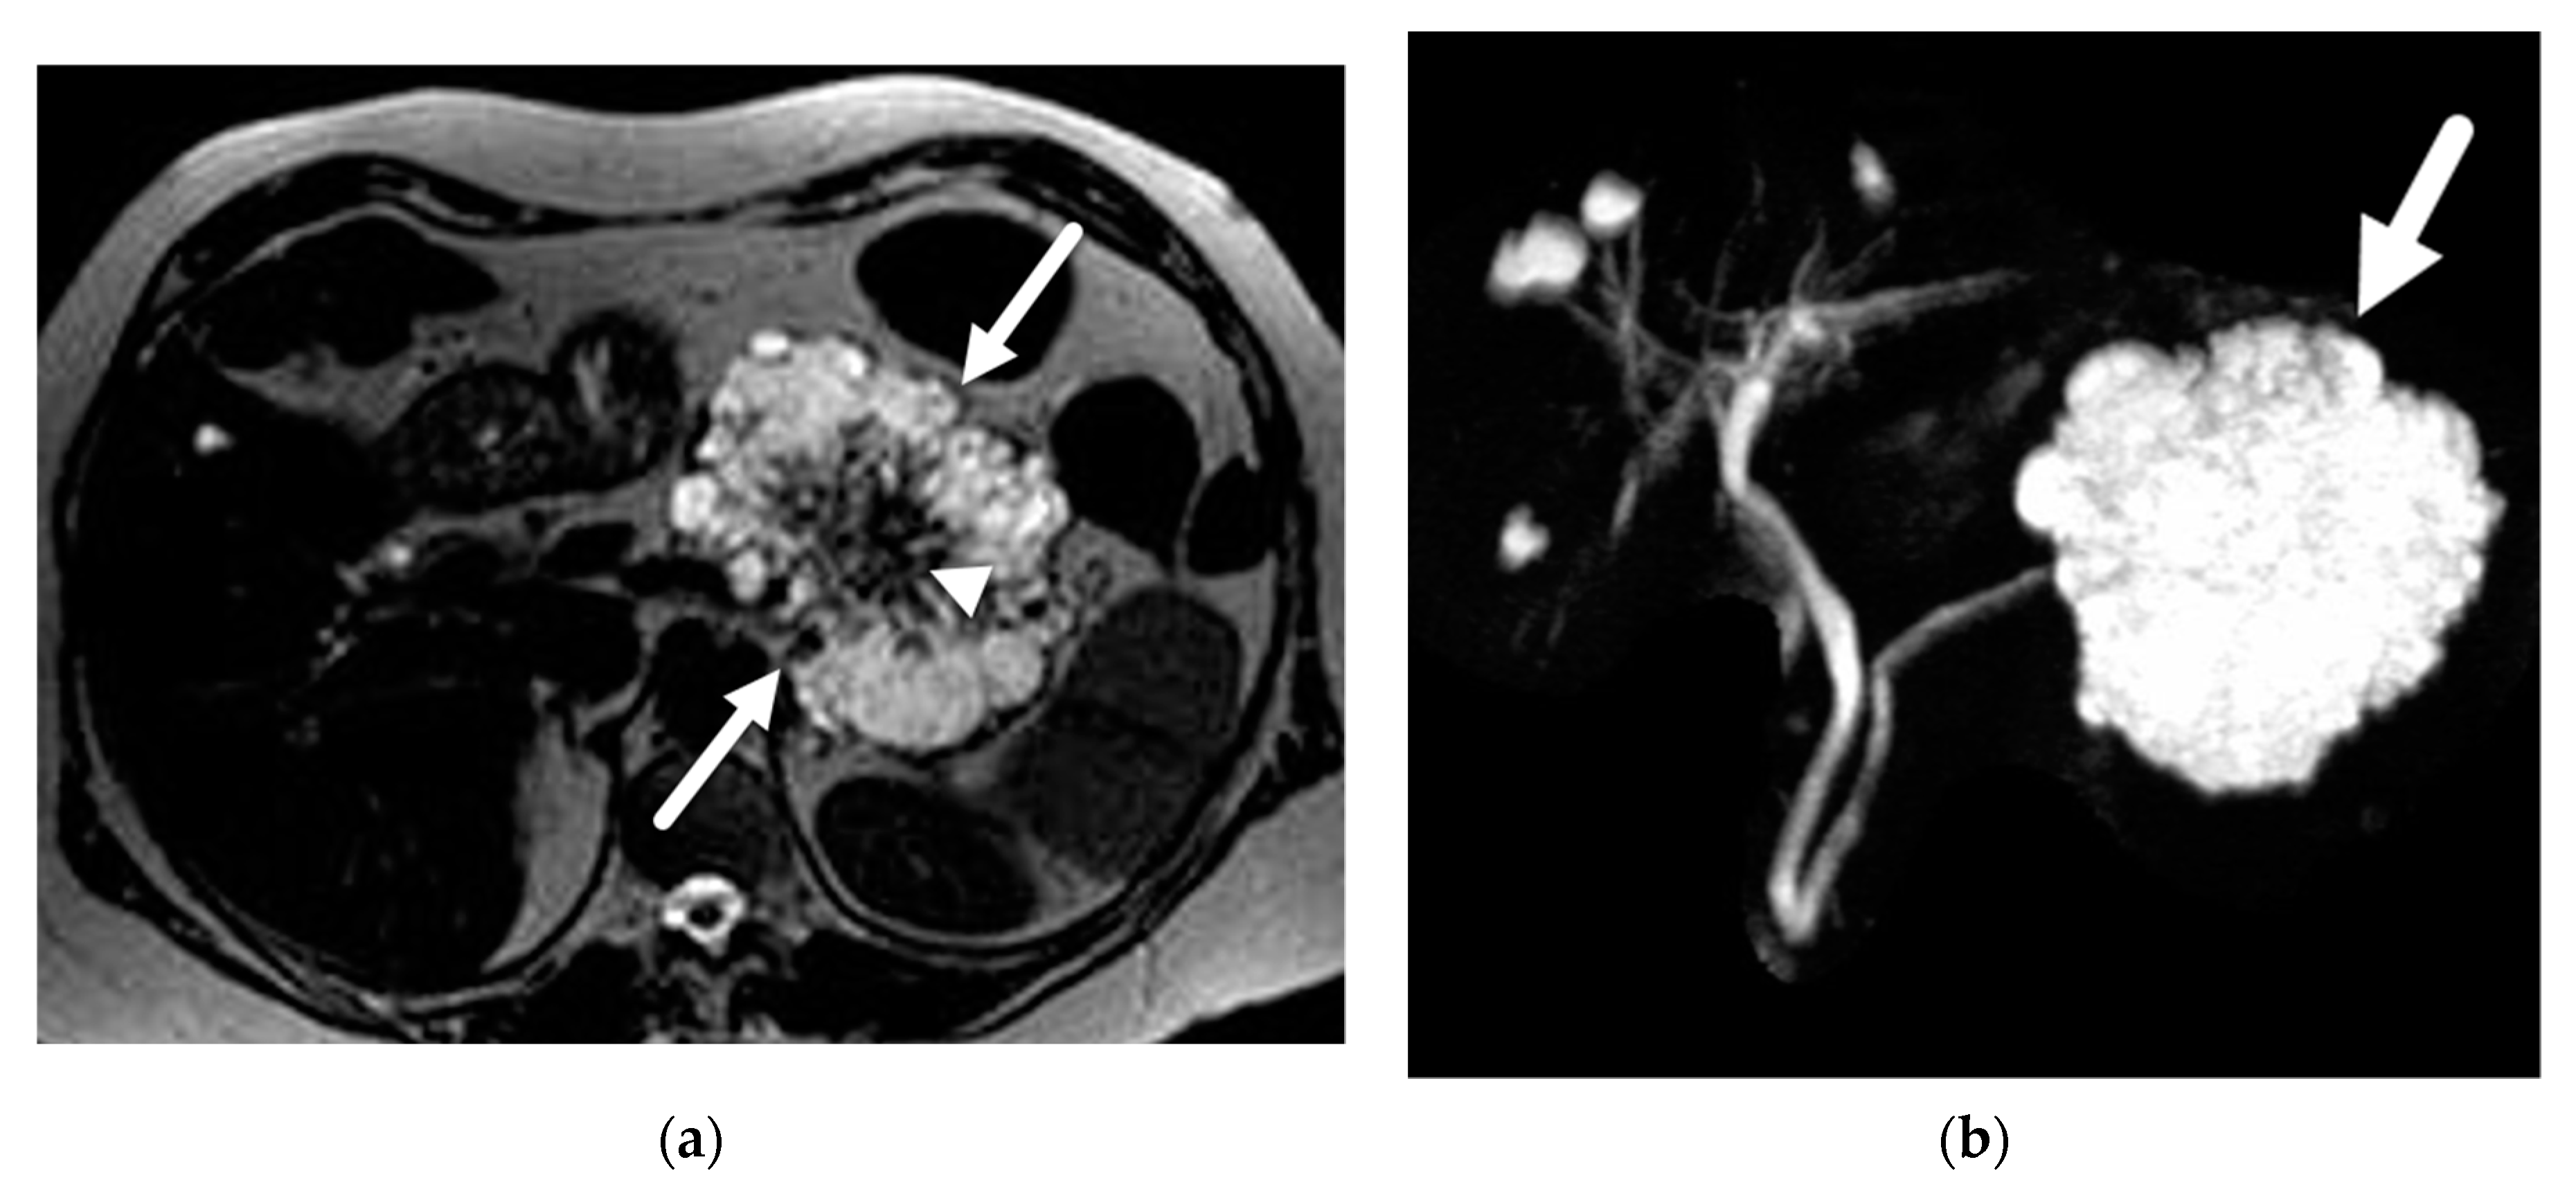

- Choi, J.Y.; Kim, M.J.; Lee, J.Y.; Lim, J.S.; Chung, J.J.; Kim, K.W.; Yoo, H.S. Typical and atypical manifestations of serous cystadenoma of the pancreas: Imaging findings with pathologic correlation. AJR Am. J. Roentgenol. 2009, 193, 136–142. [Google Scholar] [CrossRef] [PubMed]

- Giambelluca, D.; Bruno, A.; Picone, D.; Midiri, M. The honeycomb pattern of pancreatic serous cystadenoma. Abdom. Radiol. 2019, 44, 1191–1192. [Google Scholar] [CrossRef]